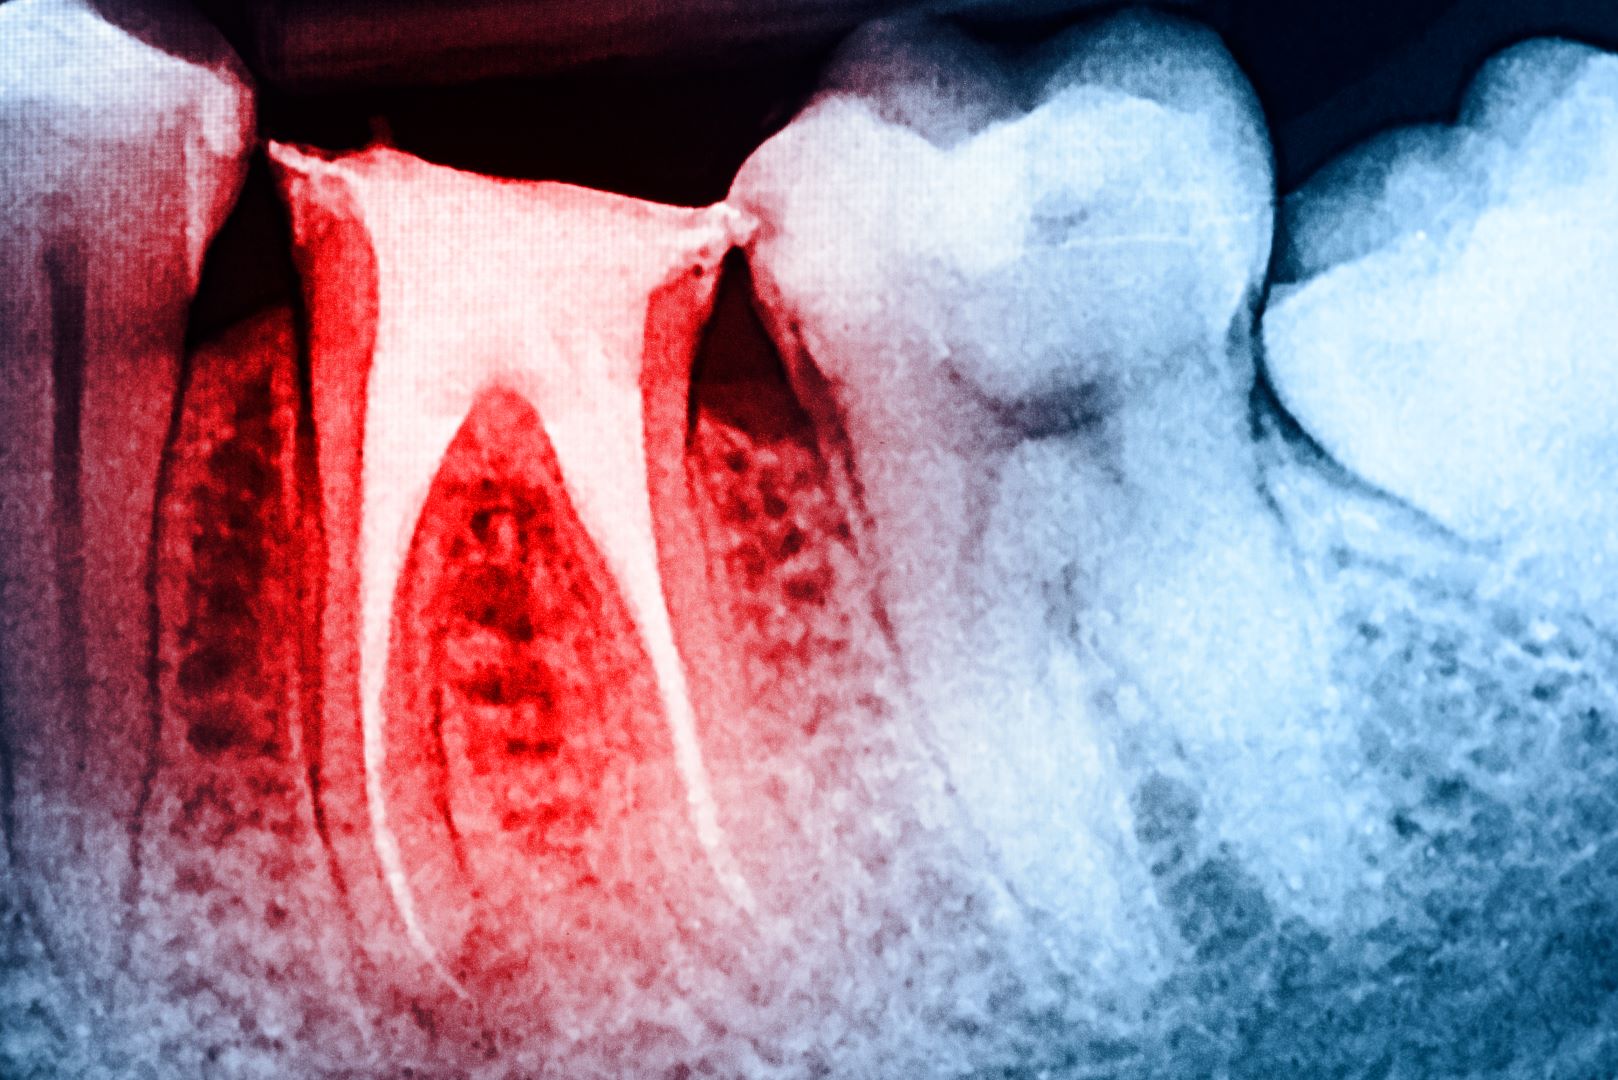

Being sensitive after having a root canal treatmentcan make you worry, more so if you thought that the procedure would lessen pain instead of increasing it. In the coming paragraphs, we will talk about why sensitivity happens following a root canal, give advice on how to handle discomfort after the treatment has been done and what steps are necessary for when this feeling doesn’t go away; finally we explore how dental professionals may assist in reducing post-root canal sensitivityfor good.

Feeling sensitive after having a root canaltreatment is not strange; it might happen due to these explanations:

- Inflammation:Inflammation can make the surrounding tissues become swollen, which might lead to a bit of discomfort when you are having a root canal treatment.

- Tissue Healing:The ongoing growth and repair of tissues after a root canal therapy might lead to slight soreness or responsiveness.

- Microleakage:In few situations, bacteria can come back and lead to sensitivity due to microleakage or inadequate sealing of the tooth’s root canal system.